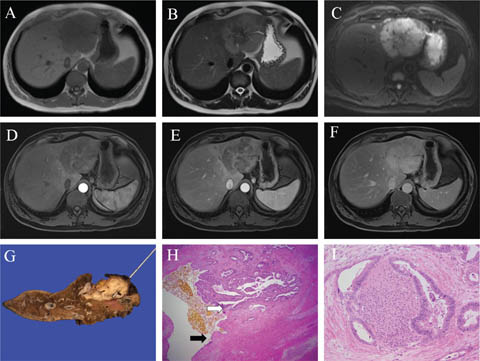

Fig 1

Figure 1. Representative images of focal nodular hyperplasia. A. On portal phase CT in liver windows the isoenhancing lesion with hypoenhancing central scar in segment 2/3 is subtly appreciated (white arrow to the edge of lesion), subtly bulging the inner contour of the left lobe, a so-called “stealth” lesion. B and C. On MRI in a different patient, a similarly located segment 2/3 lesion is isointense with the background liver on the T1 weighted image (B) and T2 weighted image (C). D and E. Following intravenous gadoxetic acid administration, the lesion shows homogenous hyperenhancement during the arterial (D) and portal (E) phases. F. On the hepatobiliary phase at 20 minutes, the lesion shows uniformly higher signal than the background liver. G and H. A partial hepatectomy from a separate patient shows a well-circumscribed lesion with a central stellate scar (white arrow) and radiating fibrous septae, seen grossly (G) and microscopically (H). I. Ductular reaction (black arrow) is present at the interface of fibrous regions with nodules. Slides are stained with Hematoxylin and Eosin. Total image magnification: H - 25X; I - 100X.

FNH can be subtle on unenhanced imaging, due to the benign hyperplastic tissue blending in with adjacent liver parenchyma, classically described as a “stealth lesion” (8). On ultrasound, the central scar may be indistinctly visualized; otherwise, FNH echogenicity is varied and nonspecific. However, contrast-enhanced ultrasound, CT, or MRI is usually diagnostic. The central feeding artery with centrifugal flow may be seen as the characteristic “spoke-wheel” pattern on color Doppler, CEUS, and sometimes CT arterial phase, most commonly in larger lesions (9). FNH is typically a subtle hypoattenuating or isoattenuating homogenous lesion on unenhanced CT. On multiphasic CT, the arterial phase is most diagnostic for FNH, with homogenous enhancement and hypoattenuating central scar, if present. On the portal-venous phase, enhancement is subdued, appearing mildly hyperattenuating or isoattenuating to the liver with the scar remaining hypoattenuating. On delayed phase imaging, the scar is typically hyperenhancing, with the remainder of the lesion isoattenuating.

MRI provides the most diagnostic characterization of FNH (with a specificity of 98%) (10). FNH is T1-weighted imaging (T1WI) isointense or slightly hypointense, and T2-weighted imaging (T2WI) isointense or slightly hyperintense. If present, the central scar is T1WI hypointense and T2WI hyperintense. Similar to CEUS and CT, during the arterial phase, FNH demonstrates intense homogenous enhancement (sparing the central scar), is relatively isointense on portal-venous phase (hypointense scar), and isointense on delayed phase (hyperintense scar). Gadoxetic acid-enhanced MRI is sensitive for FNH, showing a high signal on the hepatobiliary phase at 20 minutes, which aids in differentiation from other arterial enhancing liver lesions, such as adenomas (11).